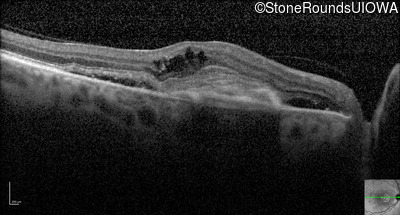

Optical Coherence Tomography - Right - 20/250